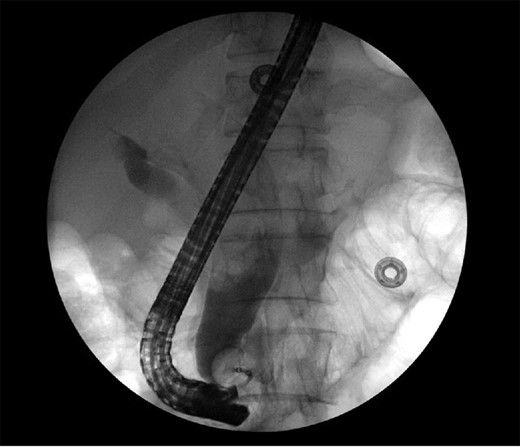

The patient is a 63-year-old Chinese male who presented with lethargy, 10-pound weight loss and painless jaundice for 1 week. Patient had a prior episode of jaundice of unclear etiology 2 years prior treated medically and had just emigrated from China 1 month prior to admission. Patient was febrile to 102.4°F, jaundiced with a total bilirubin of 18.5 mg/dL. Abdominal ultrasound showed intra and extrahepatic bile duct dilation, the distal CBD was dilated to 25 mm. Patient underwent endoscopic retrograde cholangiopancreatography (ERCP), which showed thick yellow mucus and no stones (Fig. 1). A sphincterotomy was performed and a pigtail stent placed. Computed tomography (CT), magnetic resonance imaging and magnetic resonance cholangiopancreaticogram failed to show a pancreatic head mass, distal CBD mass or stones causing obstruction (Fig. 2). Cold forceps biopsy of the papilla, endoscopic ultrasound with fine needle aspiration biopsy (FNAB) of pancreatic head, and CBD brushings were all nondiagnostic. CBD stents occluded two times in 2 weeks’ time secondary to thick mucus, requiring multiple ERCPs with stent exchanges (Fig. 3). After extensive multidisciplinary discussions regarding unclear etiology of distal CBD obstruction and extensive discussion with patient and family, the decision was made to perform a Whipple procedure for diagnosis and definitive treatment. Intraoperatively, choledochoscopy was performed, which showed very thick yellow mucus and frond-like mucosa near the ampulla. Final pathology showed a 2.0 × 1.5 × 0.5 cm3 granular lesion in the distal CBD. There was prominent biliary epithelial proliferation with tubular–papillary architecture and minimal nuclear atypia in association with chronic inflammation, stroma reaction and smooth muscle proliferation. The overall histological change in the distal CBD resembled that of AH seen in gallbladder, likely non-neoplastic change (Figs 4 and 5). At 1 year follow-up, he is doing well and his jaundice has resolved.

CT of the abdomen and pelvis showing severely dilated intra and extrahepatic bile ducts.